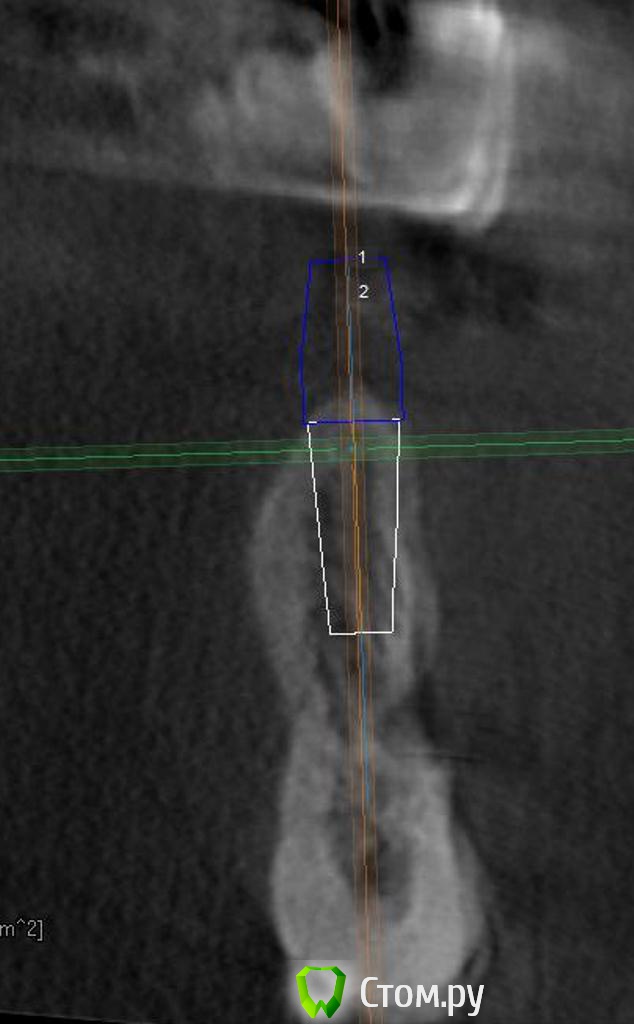

bilal Опубликовано 8 апреля, 2014 Поделиться Опубликовано 8 апреля, 2014 2 месяца назад установил имплан в позиции 3.5 пациенту. При установке с вестибуляроной сороны верхняя часть импланта была неприкрыта костью в 2-3 мм. Проводил НКР и зашил под заглушку. Сегодня при осмотре с вестибулярной резьба импланта просвечиват через десну в 1-2 мм, как-будто графт рассосался.Какой из этих вариантов больше приемлем на ваш взгляд:1. Открыть сейчас, повторить НКР и зашить;2. Повторить НКР плюс ФДМ;3. Посадить ССТ плюс ФДМ.Заранее благодарю Ссылка на комментарий

Strelok96 Опубликовано 9 апреля, 2014 Поделиться Опубликовано 9 апреля, 2014 3 вариант, хотелось бы увидеть фото и кт после. Ссылка на комментарий